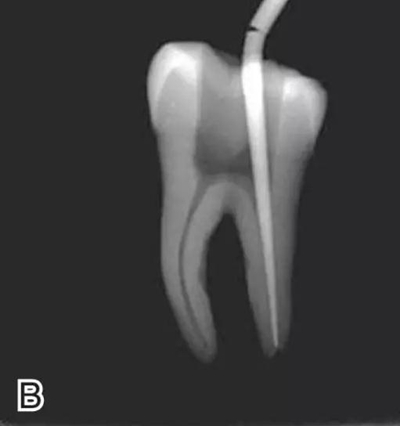

3、試尖

選擇非標(biāo)準(zhǔn)牙膠尖(如0.04、0.06 錐度牙膠尖)作為主尖,型號一般與根管預(yù)備最大號的器械型號一致,能到達(dá)距根尖0.5~1 mm 處,主尖尖段與根管壁緊密接觸。拍試尖X 線片進(jìn)行確認(rèn)(圖3)。

圖3 試尖,A.試主尖 B.拍試尖X片